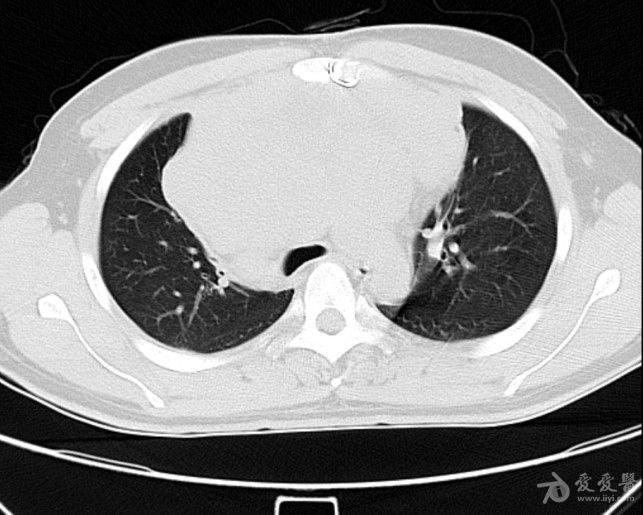

病例19恶性胸腺瘤

图片尺寸651x453